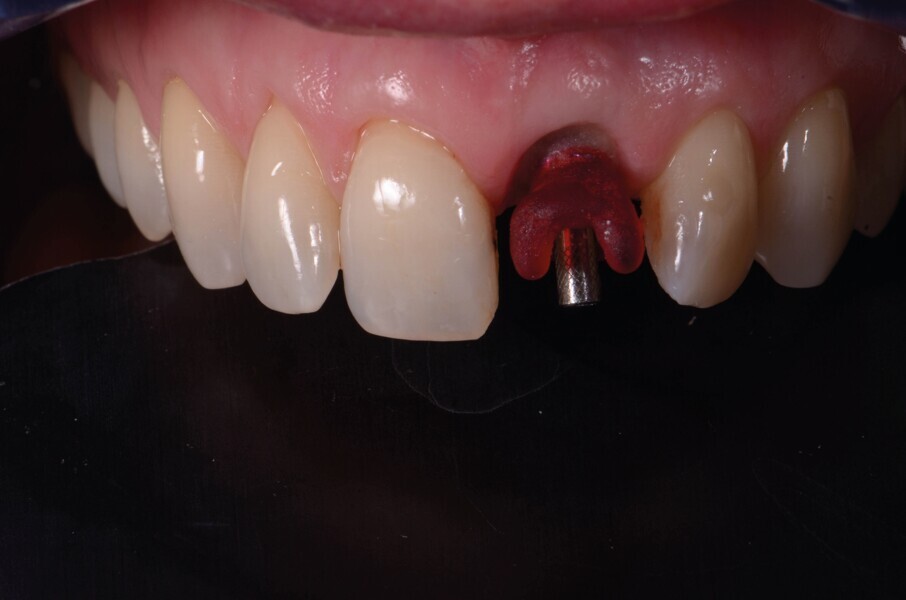

Fig. 13a : Immédiatement après la pose de l’implant.

Un implant (Aadva Regular, GC Tech), avec une connexion conique interne associée au concept du platform switching, est mis en place (Figs. 11–12). La dent provisoire est ensuite collée à nouveau aux dents adjacentes

(Fig. 13a). Au bout de quatre mois, l’ostéointégration de l’implant est obtenue et cette fois encore, les tissus mous sont bien intégrés (Fig. 13b). La phase prothétique peut alors débuter.